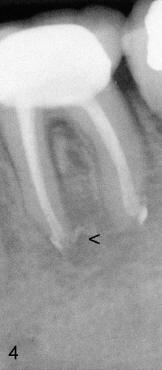

A 31-year-old otherwise healthy Chinese lady has had discomfort since RCT was done for the tooth #19 in home country ~2 years ago (Fig.1). Gutta percha (GP) appears to extrude both in mesial (<) and distal (<<) canals, surrounded by periapical radiolucency (PARL). Two carpules of 2% Lidocaine with 1:100,000 Epinephrine are used for RCT retreat. The patient does not experience any sharp pain during the first injection. Two rubber dams are used due to the short clinical crown of #19 (Fig.2,3). Fig.2 shows master cones (30/.06 M, 40/.06 D) after removal of existing gutta percha using Chloroform. It appears that extruded mesial GP remains outside the apex (< in Fig.2). It is confirmed after removing master cones (< in Fig.3). Working length is controlled by Apex locator during canal re-shaping using GT rotary files. In attempt to remove apparent GP in mesial canal(s) and extruded one outside the apex, #15 hand file is reused at WL+1mm with Chloroform for one or twice for each canal. After adjusting distal GP length, cold lateral condensation is finished with AH26 plus paste and pre-existing PFM crown is recemented (Fig.4). It is apparent that the previously extruded GP is not removed (< in Fig.4).